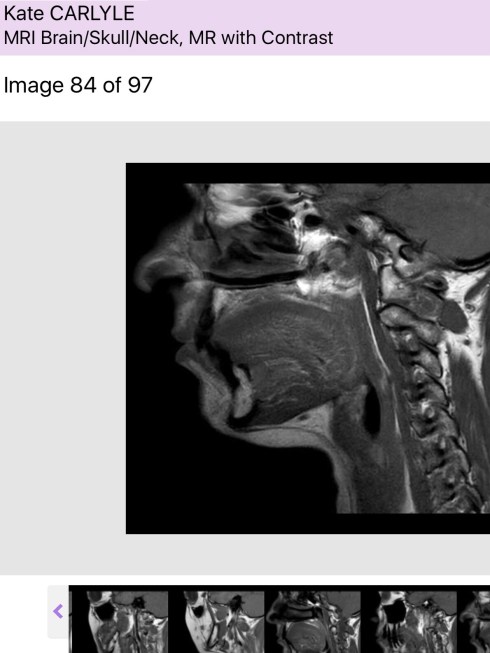

I truly believe that, which is why I’m not completely terrified of a ‘suspicious mass’ recently discovered in my mouth.

It’s coming out in a few days time. The surgeon is highly experienced and during the necessary scans and tests of late has become a good fit in my (now rather extensive) care team.

Whilst acknowledging if this case were for his surgical exam, he would leave things for a few months, he duly pointed out that this is real life and this patient has a nasty cancer history. So, we agreed that after observing for a set period – the ‘watch and wait’ approach is clearly not in my best interests.

This may turn out to be a sublingual gland that is just ‘misbehaving’ given my overall health. Fingers crossed. If it is however, another hit of the ‘Big C’, I’ll deal with it as I have the last three.

Fortunately they won’t have to go through my face (or brain! I was shocked when he mentioned casually that sometimes that is the best/only way to get to the area), they’ll go into the floor of my mouth, through my mouth.